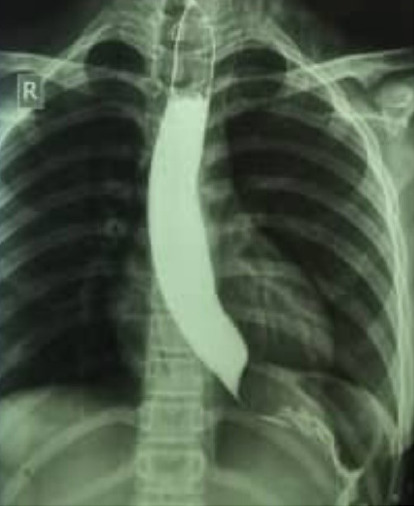

背景:食管胚胎性横纹肌肉瘤(ERMS)是一种罕见的儿童癌症,在一个涉及吞咽困难和呕吐的病例中模仿贲门失弛缓症。由于潜在的并发症,诊断和化疗需要仔细监测。病例介绍:一名12岁女孩,无既往病史,表现为进行性吞咽困难和呕吐。初步诊断为贲门失弛缓症,但进一步检查发现一个大的纵隔肿块引起食管压迫。活检证实原发性食管ERMS伴转移。尽管化疗,她出现并发症,包括中性粒细胞减少性小肠结肠炎和后部可逆性脑病综合征(PRES)。不幸的是,她死于中性粒细胞减少性败血症。结论:在本病例研究中,除了文献中有限的信息外,我们还介绍了我们对该疾病的临床病程、治疗策略和预后的经验。

Background: Esophageal embryonal rhabdomyosarcoma (ERMS), a rare pediatric cancer, mimicked achalasia in a case involving dysphagia and vomiting. Diagnosis and chemotherapy necessitate careful monitoring due to potential complications. Case presentation: A 12-year-old girl with no prior medical history presented with progressive dysphagia and vomiting. Initial diagnosis suggested achalasia, but further evaluation revealed a large mediastinal mass causing esophageal compression. Biopsies confirmed primary ERMS of the esophagus with metastases. Despite chemotherapy, she developed complications, including neutropenic enterocolitis and posterior reversible encephalopathy syndrome (PRES). Unfortunately, she succumbed to neutropenic sepsis. Conclusion: In this case study, we presented our experience regarding the clinical course of this disease, treatment strategy, and prognosis, in addition to the limited previous information in the literature.